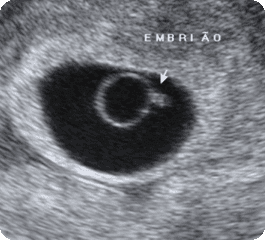

Bom dia meninas, resolvi dar uma retornada lá atrás e fazer um post sobre os primeiros três meses de gestação, quando comecei a escrever aqui no blog eu já estava com mais de três meses de gestação, e os 3 primeiros meses de gestação digamos que são "os mais importantes", é onde devemos ter uma série de cuidados e restrições, é o inicio de muitas adaptações, tanto físicas quanto emocionais.

Nos primeiros três meses você esta grávida, mas não parece grávida, muitas pessoas nem sabem da sua gravidez, mas são nestes meses que você se sente mais enjoada e também mais apreensiva.

- Neste período (quando completa-se as 12 semanas) deve-se fazer o ultra-som morfológico e a translucência nucal (clique para ver o posto sobre), neste exame são valiadas medidas do bebê que são relacionadas a possíveis síndromes e má-formações.